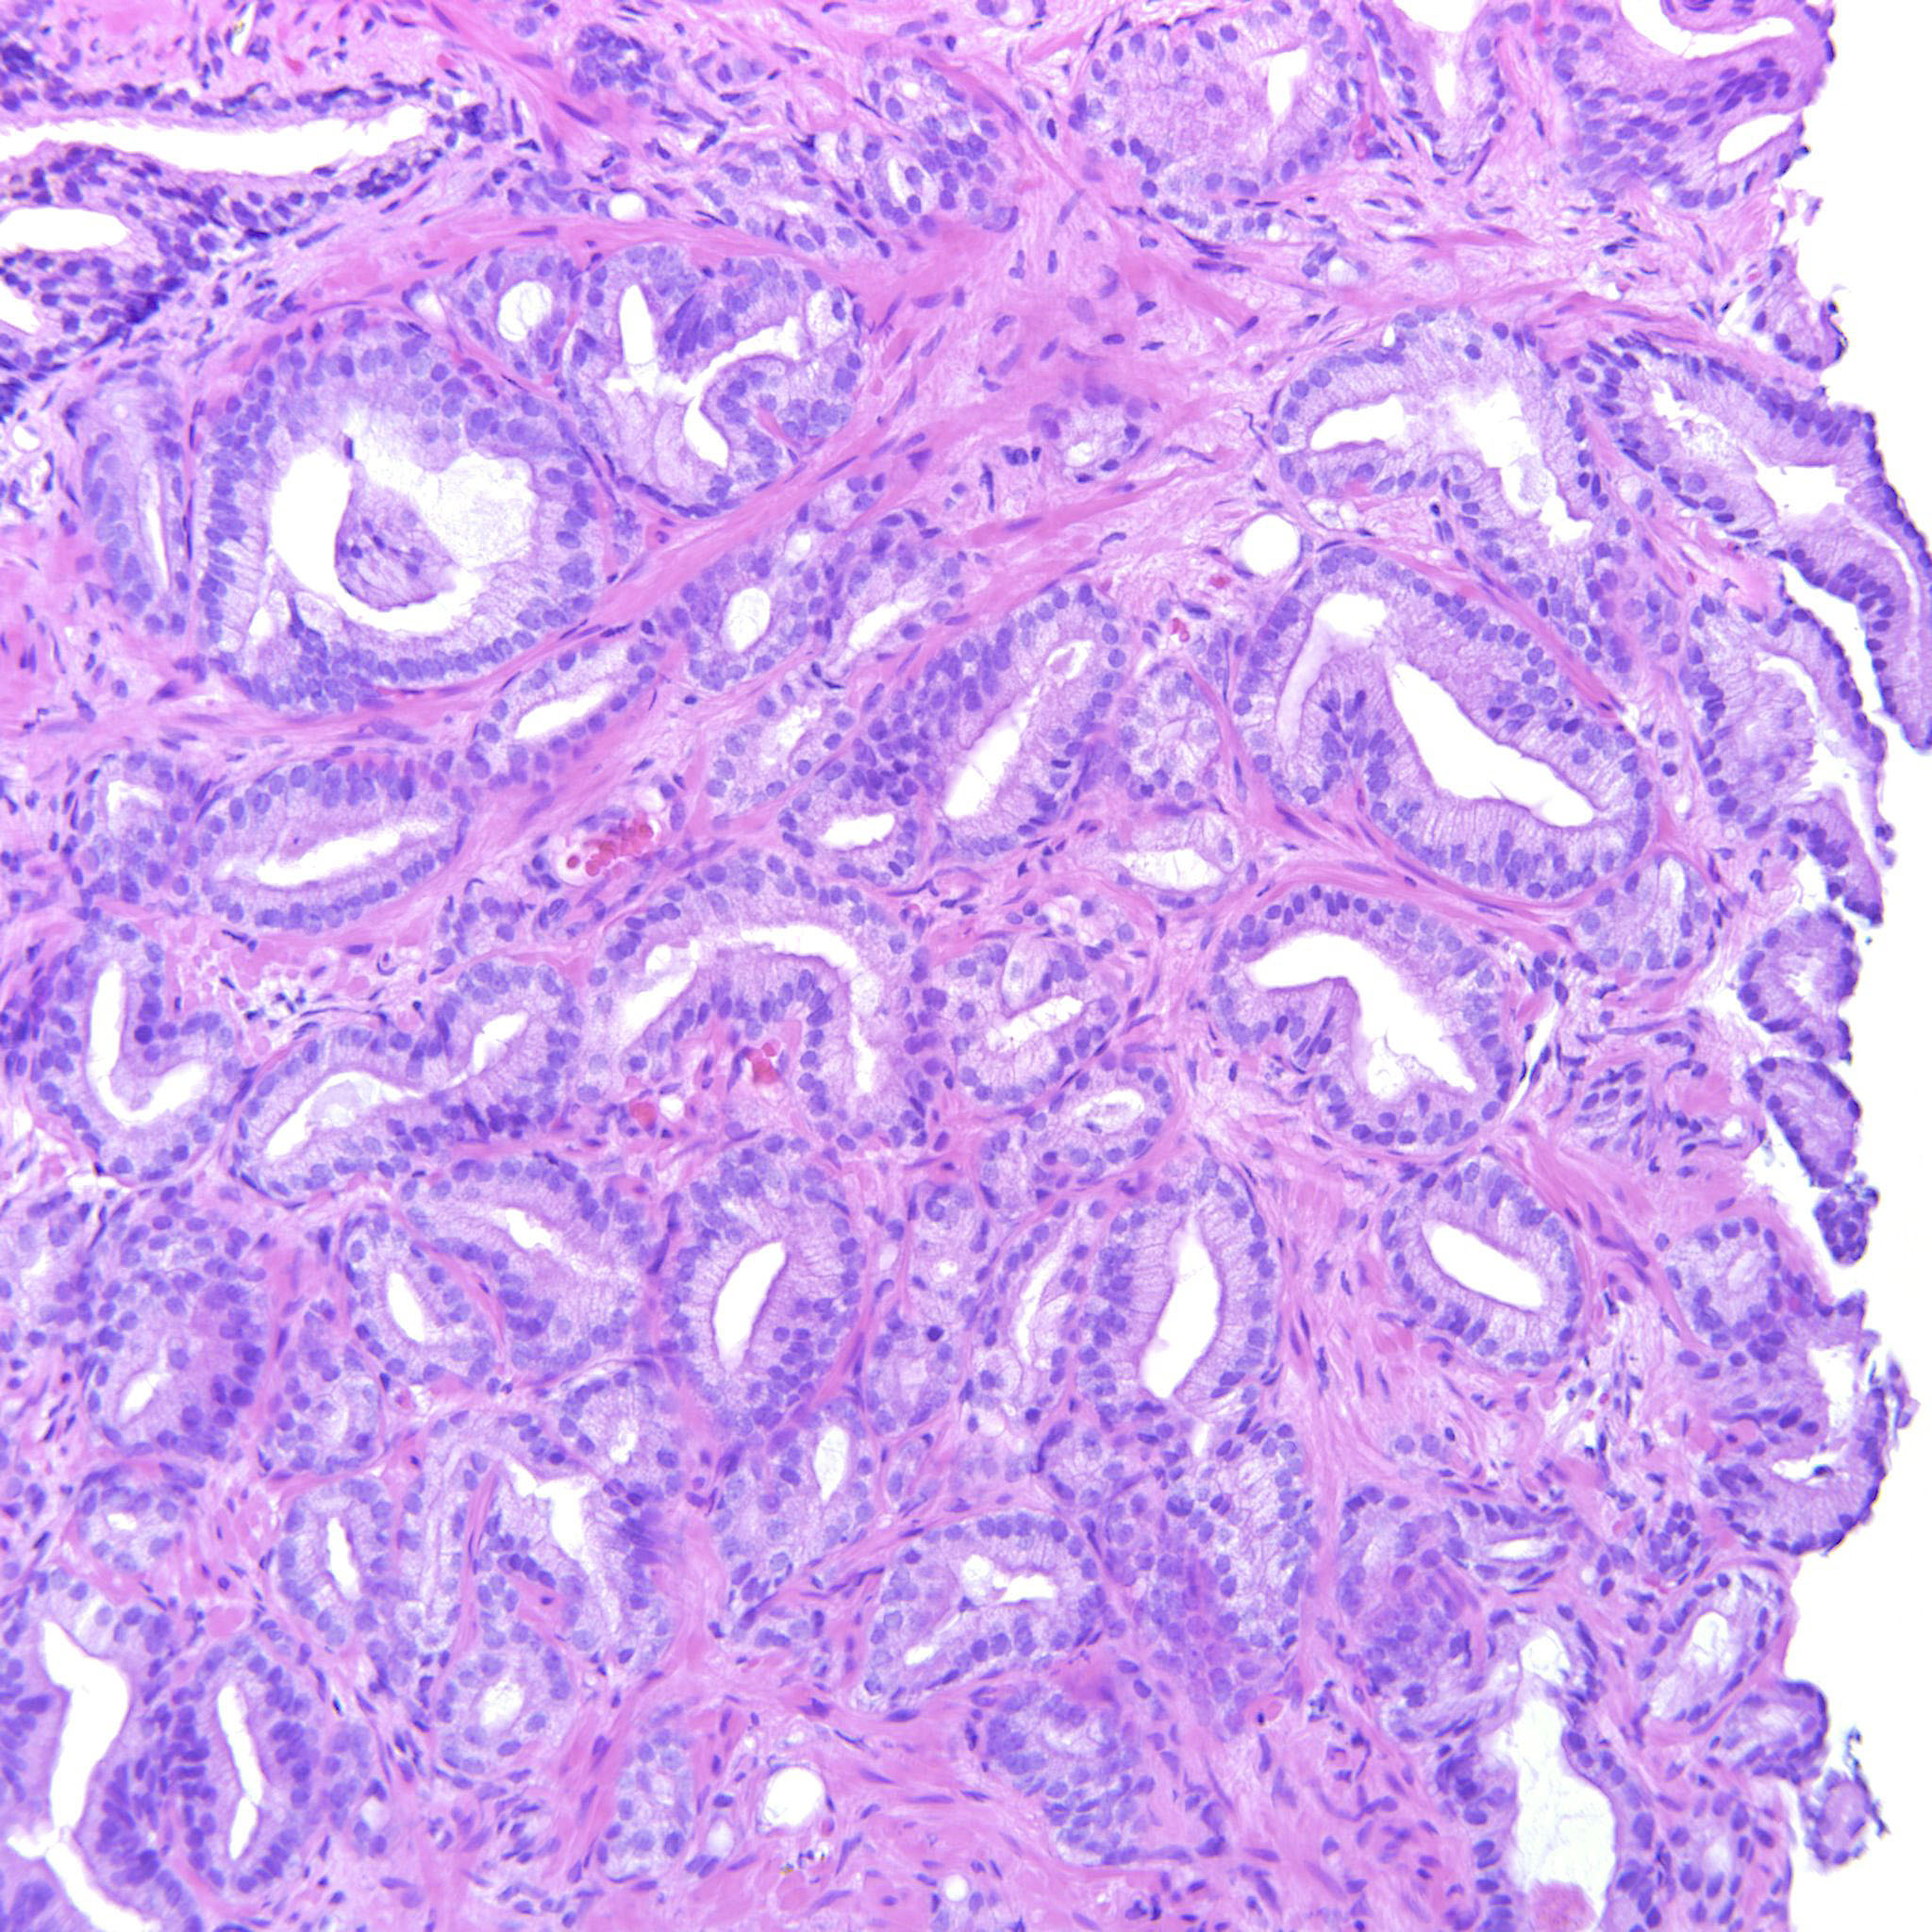

Consensus grade: GS 3+4=7 (ISUP 2)

Pathologist 1 GS 3+4=7 (ISUP 2) Borderline higher

Glands crowded but also focally fused

one could also discuss a Score 6, but there is some glomerulation and congfluence

No convincing fusion of poorly formed glands.

Mainly single glands. Some fused and poorly formed glands also

Some images only contain GP3 but there are also areas with poorly formed and fused glands justifying 347.